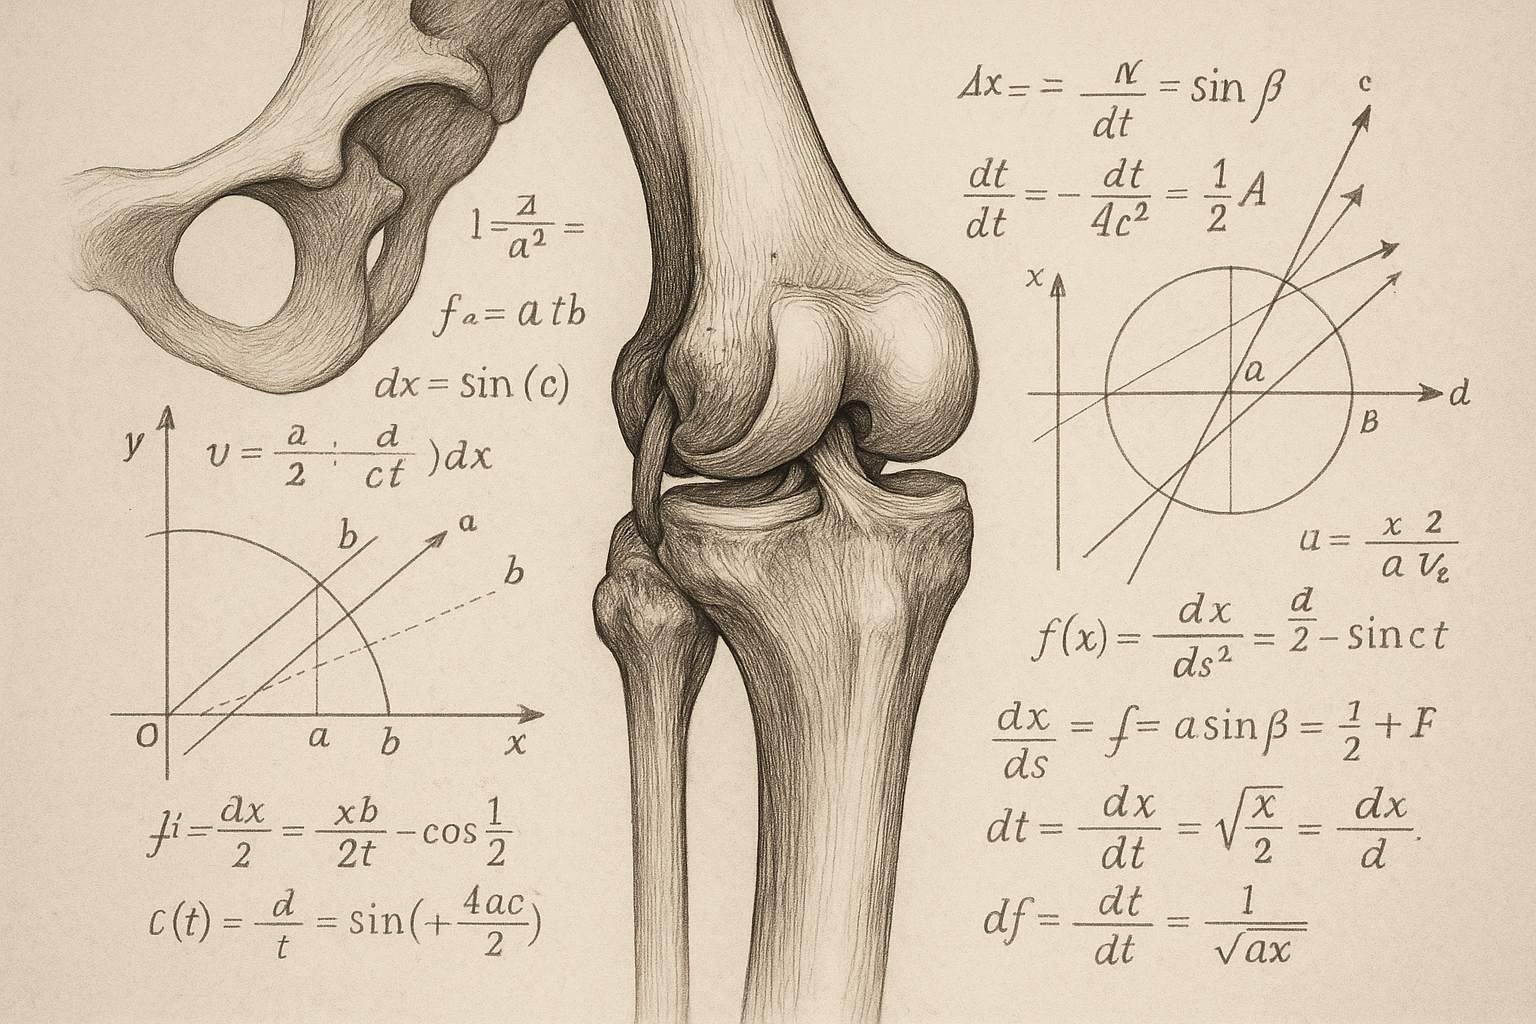

人間の身体は、関節ごとに「安定性が大切な関節」と「可動性が大切な関節」が交互に並んでいる、という理論です。

関節には役割があります。それは「安定性」と「可動性」の二つです。基本的にこれらは関節ごとに交互にならんでいます。

- 足首 → 可動性

- 膝 → 安定性

- 股関節 → 可動性

- 腰(腰椎) → 安定性

- 胸(胸椎) → 可動性

- 首(頸椎) → 安定性